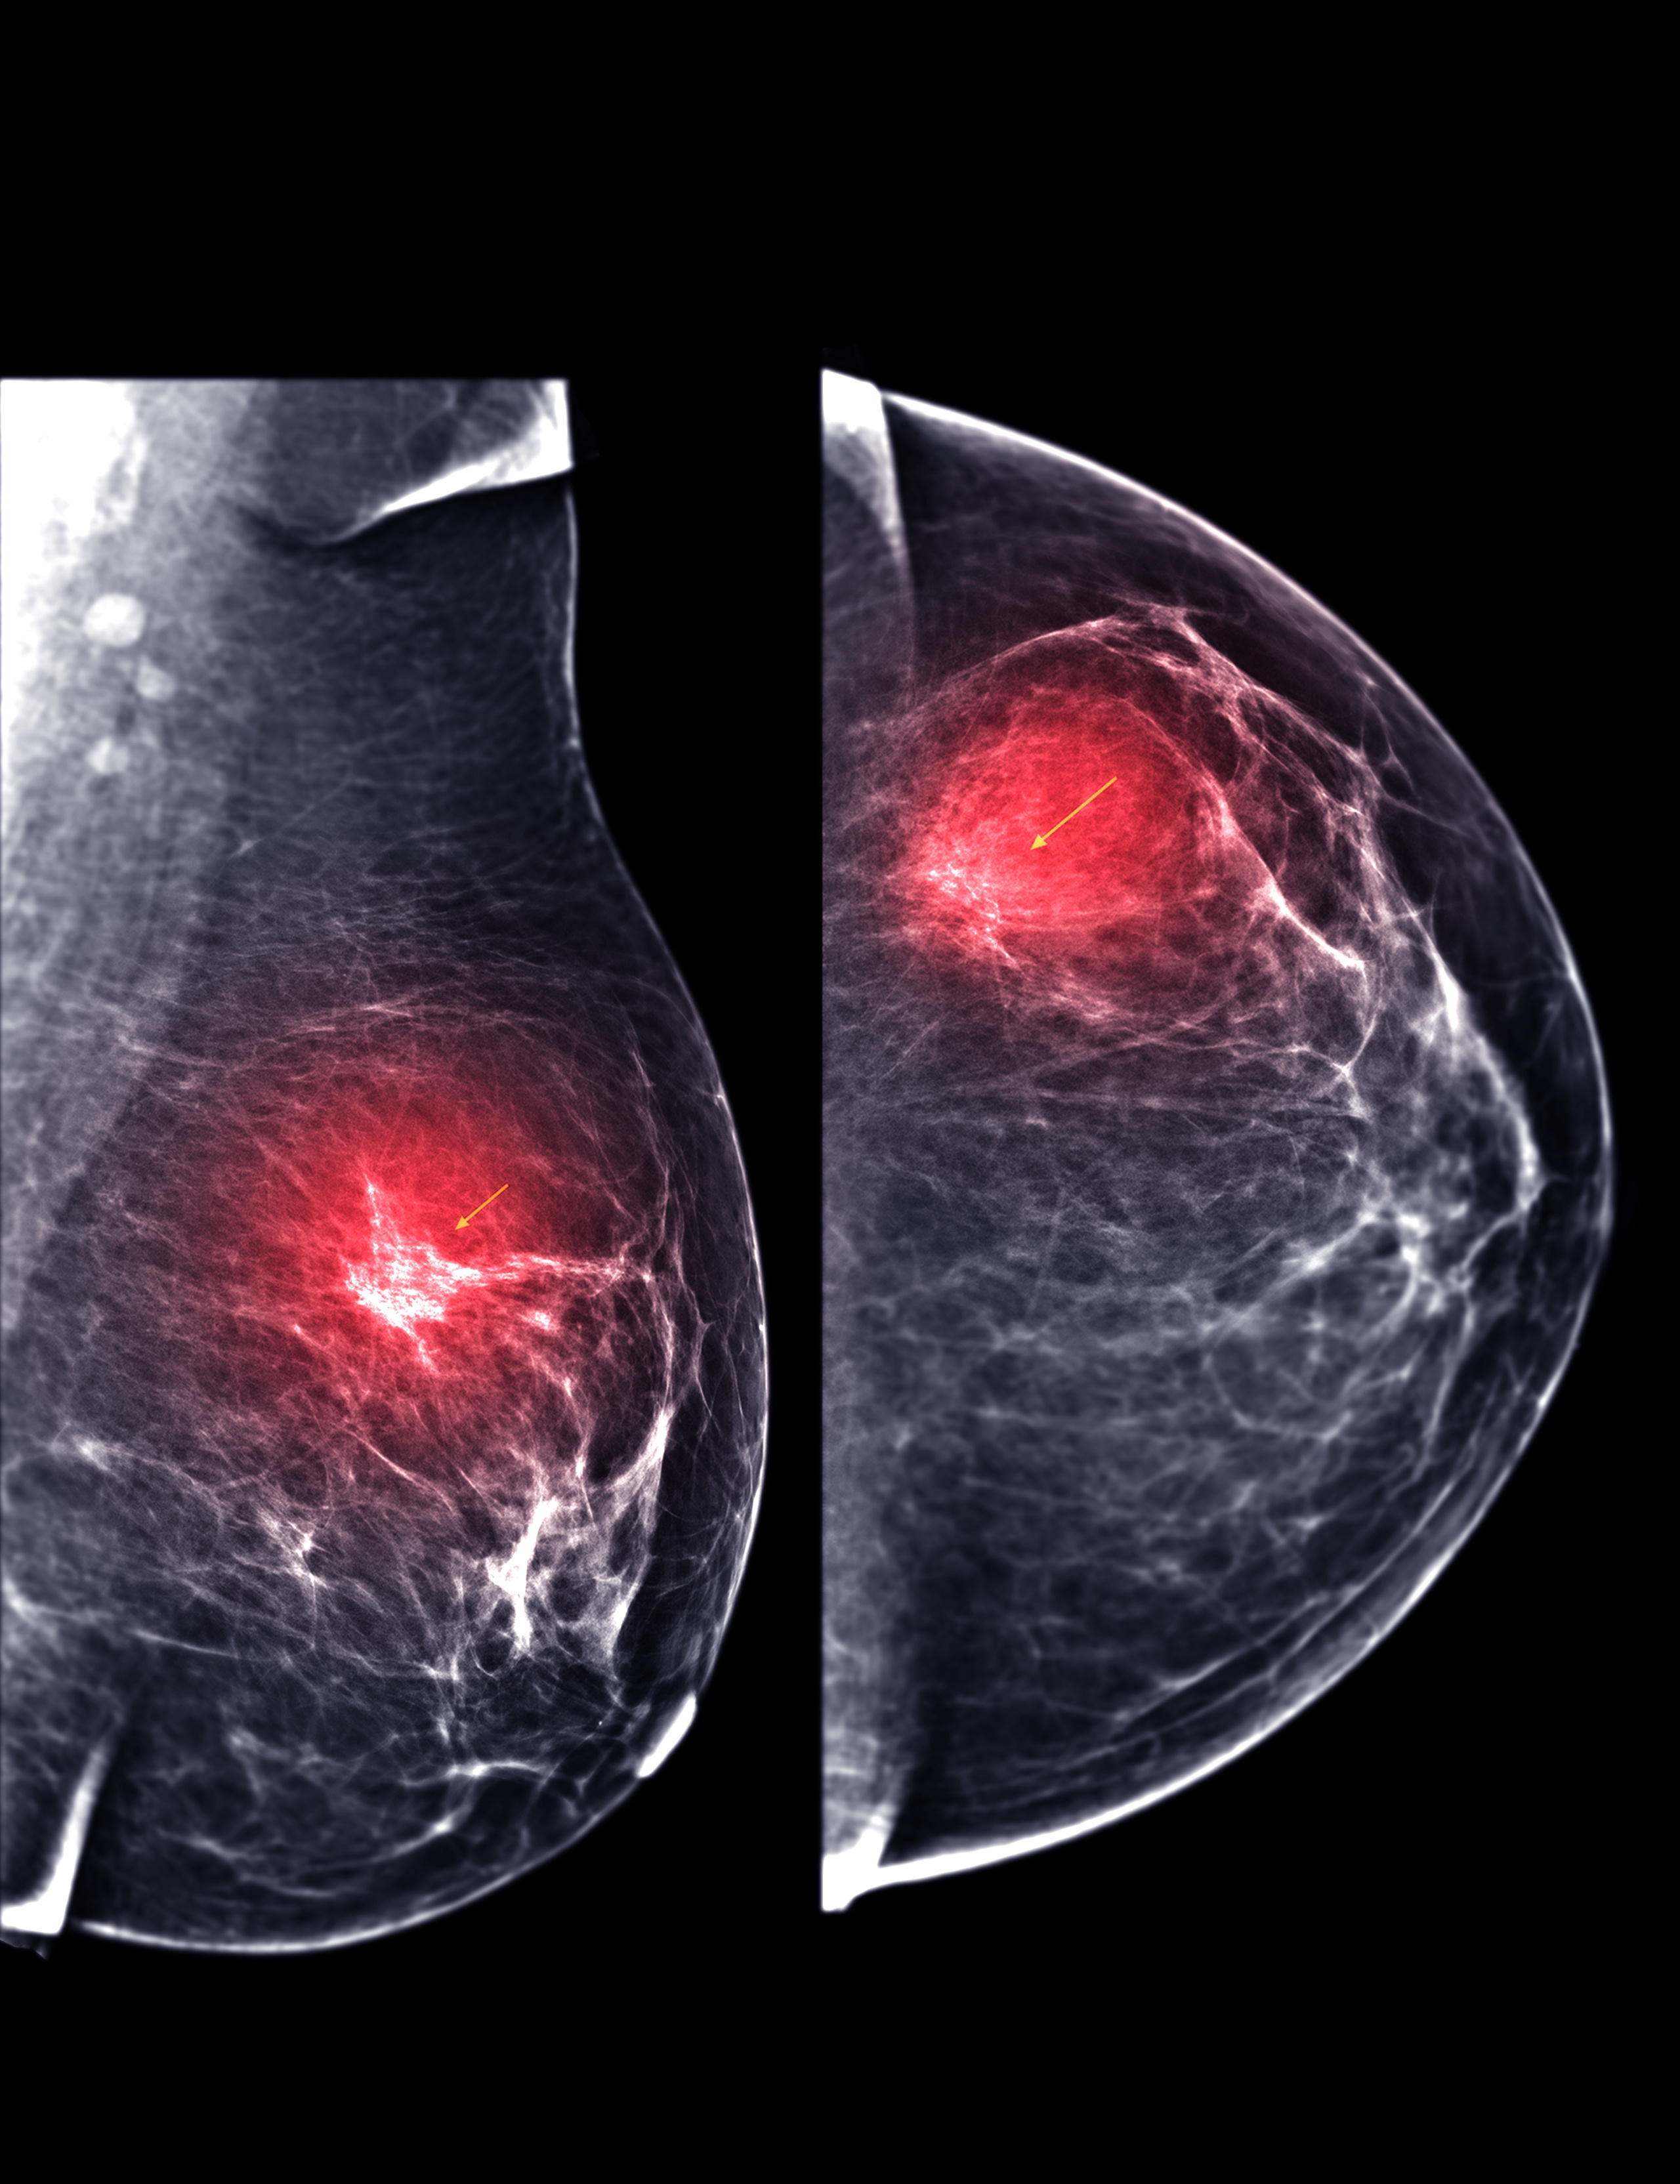

Mammogram highlighting areas of concern in breast tissue

Diagnostic imaging: Identifying suspicious areas requires both visual analysis and biological markers like hormone receptor status